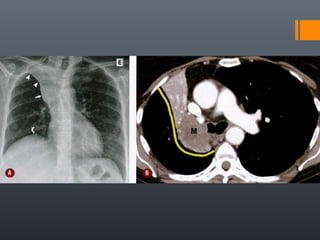

O documento discute vários conceitos radiológicos incluindo consolidação, atelectasia, nódulos, pseudocavidades e padrões intersticiais, fornecendo definições, sinais e diagnósticos diferenciais para cada tópico. Ele também discute a redução da atenuação pulmonar e fornece um link para mais informações.